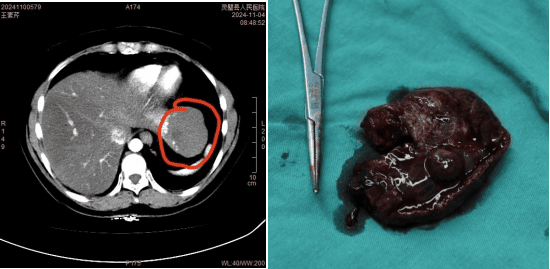

11月5日,我院普外三科运用腹腔镜微创技术,成功为肝血管瘤患者进行手术治疗,患者术后恢复良好。这是我院完成的首例腹腔镜下“左肝外叶切除术”,此次手术的成功实施,标志着我院在肝脏微创外科手术领域取得新突破。

患者53岁,腹胀伴恶心20余年,一直保守治疗。2天前于外院体检时发现左隔下脾胃前上间隙内团块软组织密度影,与肝左叶分界不清。患者及其家属至我院普外三科寻求进一步治疗。

普外三科汤军主任结合患者病史、查体以及CT等检查,初步诊断为“肝血管瘤”,拟用微创手术方式治疗。肝脏是腹腔最大的实质性器官,血管比较丰富,切除时容易出血,术中难以有效地控制。腹腔镜下肝切除术是高难度手术之一,是微创外科领域的难点。

汤军主任邀请曹葆强院长会诊指导,对患者病情及治疗进行详细评估,并制定了“腹腔镜左肝外叶切除术”方案。

经过患者和家属同意,完善术前准备后,在曹葆强院长的指导下,普外三科团队在麻醉科及手术室的共同配合下,成功开展首例腹腔镜下左肝叶切除术,在不损伤右侧肝叶的情况下,切除直径近7cm大血管瘤。术中可见肝血管瘤与左侧膈肌黏连,腔镜下完整剥离瘤体,手术顺利,出血少,术后病人恢复快,第二天即下床自主活动。

腹腔镜技术实施左肝外叶切除,具有切口小、创伤轻、出血少、恢复快、痛苦小,住院时间短等许多优点。我院普外三科立足于学科发展,以腹腔镜微创治疗为特色,常规开展腹腔镜下肝脏肿瘤切除术、肝囊肿去顶术、巨脾切除术,胆囊切除术、胆总管切开取石术等微创手术,取得良好疗效,尤其是腹腔镜联合胆道镜胆总管切开取石、经皮肝胆管穿刺引流、腹腔镜胃及结直肠恶性肿瘤根治等高难度的手术,达到了市内领先水平。